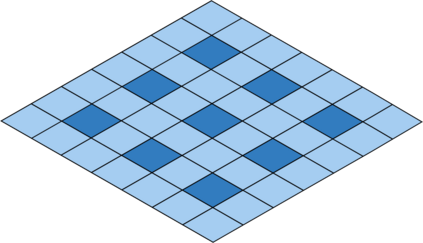

Deep Convolutional Neural Networks (DCNNs) are used extensively in biomedical image segmentation. However, current DCNNs usually use down sampling layers for increasing the receptive field and gaining abstract semantic information. These down sampling layers decrease the spatial dimension of feature maps, which can be detrimental to semantic image segmentation. Atrous convolution is an alternative for the down sampling layer. It increases the receptive field whilst maintains the spatial dimension of feature maps. In this paper, a method for effective atrous rate setting is proposed to achieve the largest and fully-covered receptive field with a minimum number of atrous convolutional layers. Furthermore, different atrous blocks, shortcut connections and normalization methods are explored to select the optimal network structure setting. These lead to a new and full-scale DCNN - Atrous Convolutional Neural Network (ACNN), which incorporates cascaded atrous II-blocks, residual learning and Fine Group Normalization (FGN). Application results of the proposed ACNN to Magnetic Resonance Imaging (MRI) and Computed Tomography (CT) image segmentation demonstrate that the proposed ACNN can achieve comparable segmentation Dice Similarity Coefficients (DSCs) to U-Net, optimized U-Net and hybrid network, but with significantly reduced trainable parameters due to the use of full-scale feature maps and therefore computationally is much more efficient for both the training and inference.